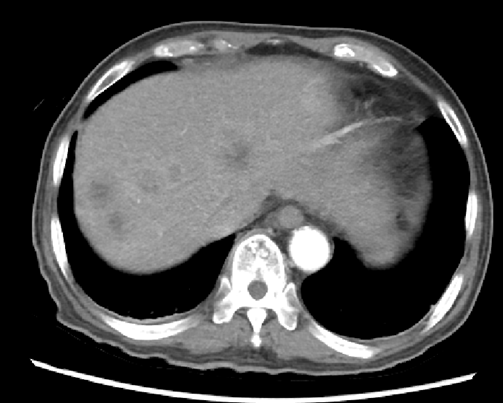

2020.4.12腹部CT:肝脏多发乏血供结节,较前明显减少并缩小(图4)。

图4. 腹部CT(左:2020.1.5,右:2020.4.12)